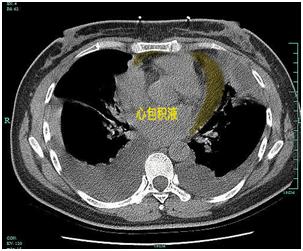

结核杆菌不仅能导致肺结核、结核性胸膜炎、淋巴结结核 , 还可能引起心包结核 。 患者一旦感染心包结核 , 会导致心脏功能受损 , 出现明显的胸闷气促、下肢水肿、乏力纳差、低热盗汗等症状 , 严重者甚至会威胁生命 。

【心脏|脚上一按一个坑!五旬大妈心上长了层“铠甲”,看医生如何化险为夷】人体的心脏好比一个“发动机” , 将充满养分的动脉血泵及全身 。 心包膜就是覆盖在心脏表面的一层“轻纱” 。 钟方明解释:这层“轻纱”会在结核菌的影响下出现发炎 , 并逐渐有炎症渗出 , 变成一件注水的“棉袄” 。 时间越久 , 积液沉积越久 , 这件“棉袄”就会变硬 , 成了“铠甲” , 紧紧地束缚着心脏 , 使心脏的搏动受限 。